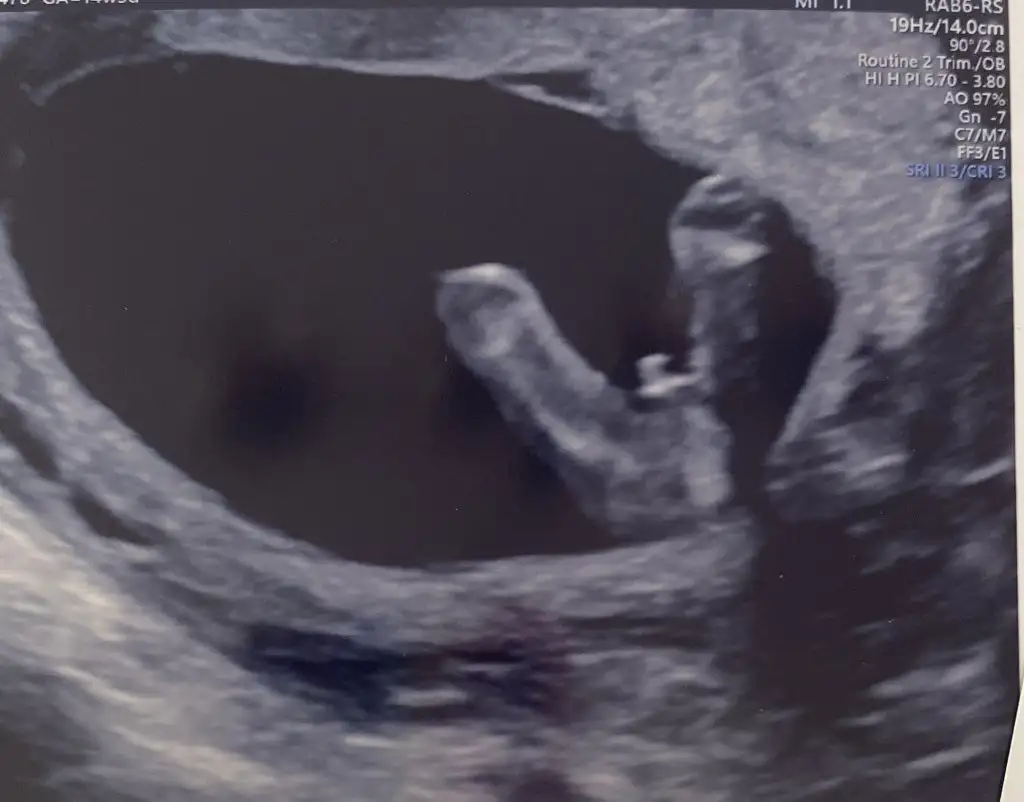

Nub, Ramzi,Çin Rus Japon Takvimleri, Yüzük Yöntemi bir çok şey size sayabilirim.

5 ve 14. haftaya kadar olan ultrason fotolarınızı paylaşın. Vajinadan mı yoksa karından mı çekildiğini ve kaç haftalık olduğunu da mutlaka belirtin.